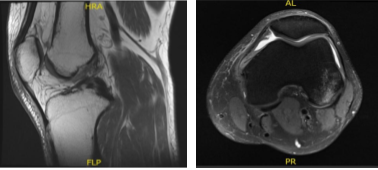

MRI – 3T Left Knee Non Contrast

MRI result was presented today and shown complex tear of the posterior horn of the medial meniscus, small horizontal cleavage tear of the body of the lateral meniscus, impaction injury of the posterior non weight bearing aspect of the lateral femoral condyle with small fracture,

Grade 2 medial collateral ligament injury with vertical longitudinal tear, Contusion in the inferior medial aspect of the patella, Moderate joint effusion with synovitis.